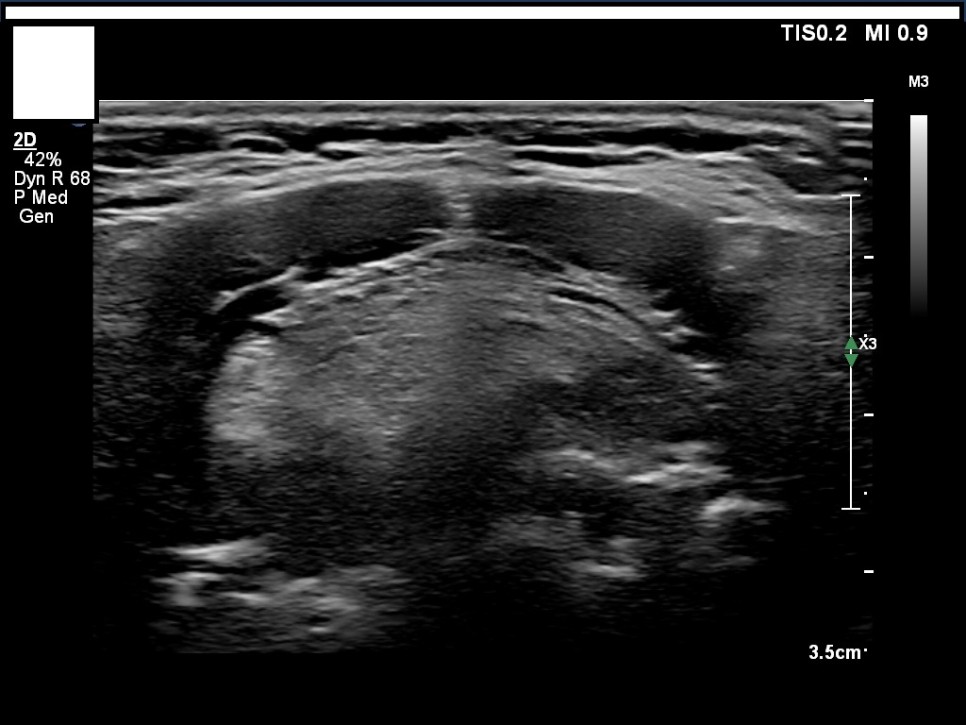

갑상선, 부갑상선 초음파 검사 급여 기준 1. 표준 영상의 범위 모든 영상에는 경부의 해부학적 위치(모식도나 문자)를 표기하여야 한다.

A) 병변이 없는 경우: 우엽 중부 가로 스캔, 우엽 중앙부 세로 스캔, 협부 가로 스캔, 좌엽 중부 가로 스캔, 좌엽 중앙부 세로 스캔, 우경부 림프절, 좌경부 림프절 나) 병변이 있는 경우: 병변이 없는 경우의 표준 영상과 함께 병변 부위에서 2개의 수직 관계 단면 영상(횡단/종단) 및 병변의 크기가 측정된 경우: 병변이 없는 경우의 표준 영상

좌측 경부 림프절 / 중심 경부 림프절 / 협부 옆 스캔 2. 판독 소견서가) 등록 번호, 성명, 생년월일 또는 연령, 성별, 검사명, 검사 일시, 판독 일시, 검사와 판독한 의사(면허 번호), 의료기관명, 검사 소견 및 결론 나) 검사 소견에는 갑상선 에코, 병변의 유무를 기술하여야 한다. 결절이 있을 경우 위치, 최대지름, 주요 소견, K-TIRADS의 내용을 기술하여야 하며, 암으로 진단된 결절을 추적할 경우 위치, 3방향 직경, 주요 소견, 전 검사와 변화 여부, 경부 림프절의 평가 및 이상 소견 여부를 기술하여야 하며, 경부 림프절에 이상이 있을 경우 위치, 크기, 주요 소견을 기술하여야 한다. 결절이 여러 개 있을 경우 암 위험도에 따라 선택적으로 기술할 수 있다. 또 소아 등에서의 환자의 협력도 음창 등이 좋지 않아 표준 영상 획득에 제한이 있는 경우 추가 기술해야 한다.